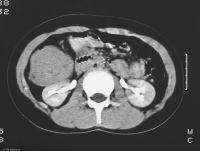

Výpočetní tomografieVýpočetní tomografie (CT - Computed Tomography) je zobrazovací metoda využívající digitální zpracování dat o průchodu rentgenového záření v mnoha průmětech vyšetřovanou vrstvou. Princip je stejný jako při klasickém snímkování - jde o zeslabení procházejícího rentgenového záření ve vyšetřovaném objektu. Svazek záření vycházející z rentgenky je vycloněn do tvaru vějíře, jehož šířka určuje šířku zobrazované vrstvy. Záření po průchodu vyšetřovaným objektem (pacientem) dopadá na detektory uložené naproti rentgence. Zde se množství dopadajícího záření převádí na elektrický signál, který dále zpracovává počítač. Během rotace jsou provedeny stovky měření, z nichž počítač rekonstruuje obraz vyšetřované vrstvy (je dán hodnotami absorpčních koeficientů z jednotlivých míst dané vyšetřované vrstvy).

CT snímek břicha.